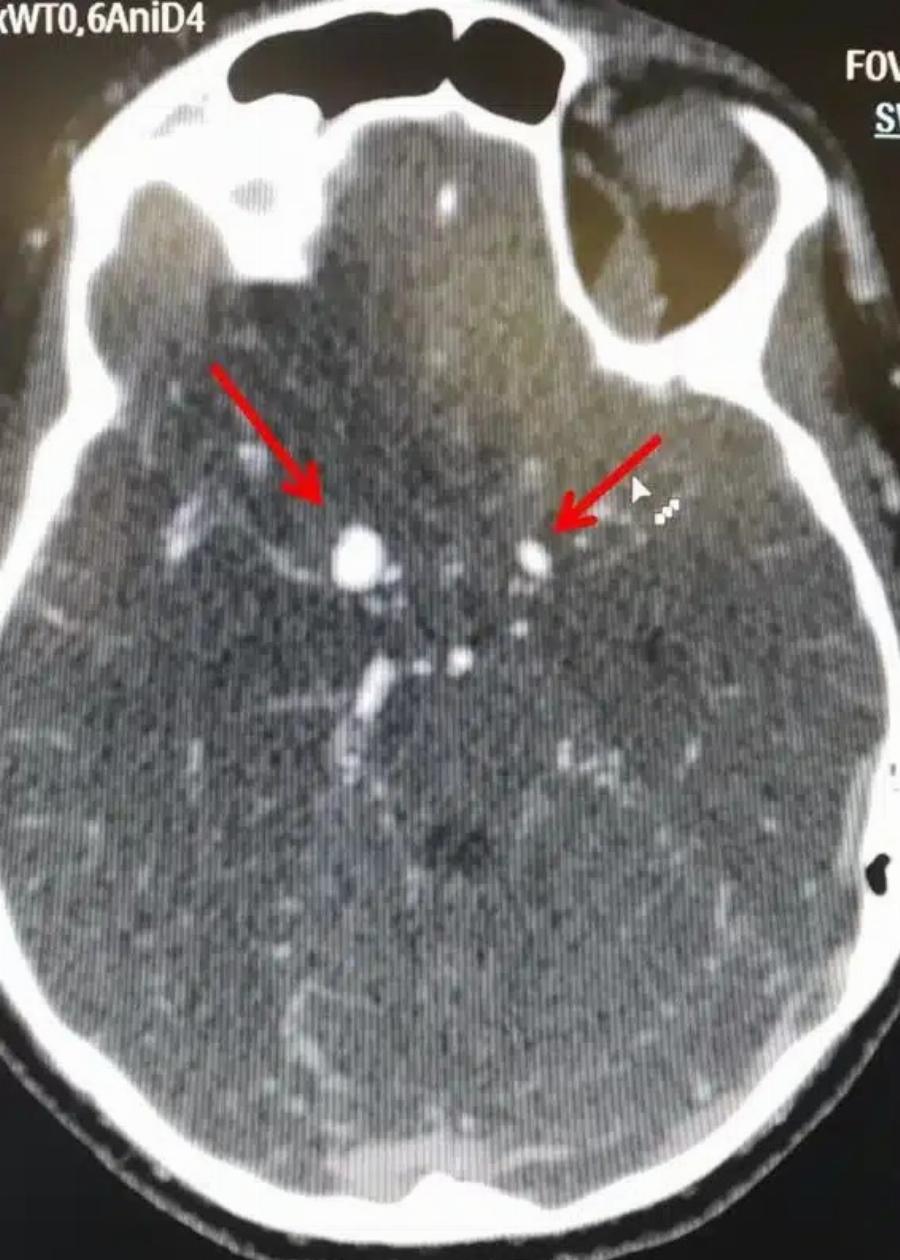

Ένα ανεύρυσμα εγκεφάλου είναι ένα εξόγκωμα ή διόγκωση σε ένα αιμοφόρο αγγείο στον εγκέφαλο.

Το ανεύρυσμα εγεκφάλου μπορεί να παρουσιάσει διαρροή ή ρήξη, προκαλώντας αιμορραγία στον εγκέφαλο (αιμορραγικό εγκεφαλικό επεισόδιο). Πιο συχνά μια ρήξη ανευρύσματος εγκεφάλου εμφανίζεται στο χώρο μεταξύ του εγκεφάλου και των λεπτών ιστών που καλύπτουν τον εγκέφαλο. Αυτό το είδος αιμορραγικού εγκεφαλικού επεισοδίου ονομάζεται “υπαραχνοειδής αιμορραγία”.

Υπάρχουν δύο μορφές εγκεφαλικών ανευρυσμάτων, το σακοειδές και το ατρακτοειδές ανεύρυσμα.

Η συχνότερη μορφή που μπορεί να πάρει ένα ανεύρυσμα είναι η ασκοειδής ή σακοειδής, δηλαδή σχηματίζεται στο αδύνατο σημείο της αρτηρίας ένας σάκος με μίσχο που τον ενώνει με την υπόλοιπη αρτηρία. Φαίνεται σαν ένα μούρο που προβάλλει από μια αρτηρία. Συνήθως αναπτύσσεται σε περιοχές διχασμού αγγείων.

Εκτιμάται ότι 3,5% έως 6% του γενικού πληθυσμού έχουν σακοειδές ανεύρυσμα. Στο 15% έως 30% των περιπτώσεων αυτών, υπάρχουν περισσότερα από ένα σακοειδή ανευρύσματα.

Πιο σπάνια το ανεύρυσμα αρτηρίας του εγκεφάλου μπορεί να πάρει μια στενόμακρη μορφή που περιλαμβάνει όλο το τοίχωμα της αρτηρίας και από τις δύο μεριές (ατρακτοειδής μορφή).